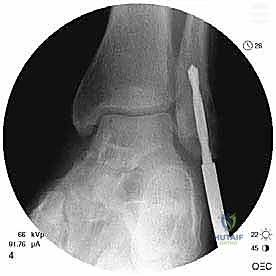

الخطوة 5: إعادة بناء وتثبيت الرباط (Retinaculoplasty)

يتم سحب الرباط (أو شريحة السمحاق) وتثبيته بقوة في العظم باستخدام خطاطيف جراحية دقيقة (Suture Anchors) مصنوعة من التيتانيوم أو مواد قابلة للامتصاص. هذا يضمن عدم وجود أي مساحة للأوتار للانزلاق مجدداً.

الخطوة 6: الفحص النهائي والإغلاق التجميلي

قبل إغلاق الجرح، يقوم الدكتور هطيف بتحريك الكاحل بقوة في جميع الاتجاهات (اختبار الاستقرار الديناميكي) للتأكد من ثبات الأوتار المطلق. ثم يتم إغلاق الشق الجراحي بطبقات تجميلية لتقليل الندبات.